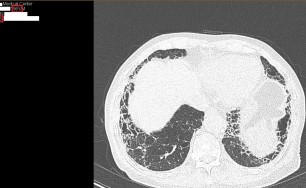

비결핵항산균에 감염된 폐사진